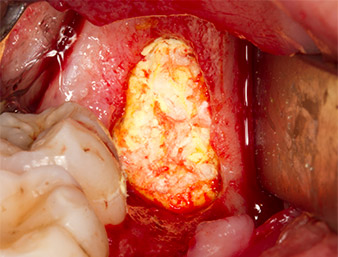

To obtain autogenous material for subsequent wound treatment, healthy bone chips were harvested from the surroundings of the root remnant with a piezo surgical instrument (Piezomed B5) (Fig. 5).

The autogenous tissue was removed with the scraper-shaped section of the working part of the instrument and stored in a physiological saline solution until further use (cf. Fig. 13).